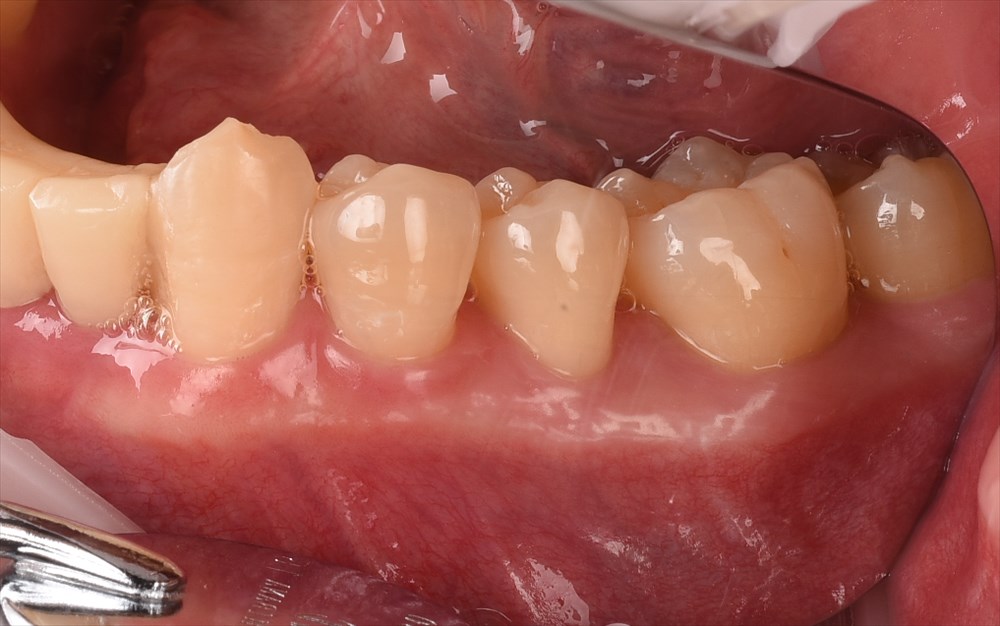

右下の6番 膿が出ていました。。。

ここは垂直的に骨が無くなっていました。ポケットは7mm。

右下6番だけは

依然7mmのポケットが残っていましたので再生療法を行いました。

マイクロサージェリーとエルビウムヤグレーザーのコンビネーションで

MISTOPEを行い2mmのみの切開→だから痛くない!

だから縫合もここだけ。